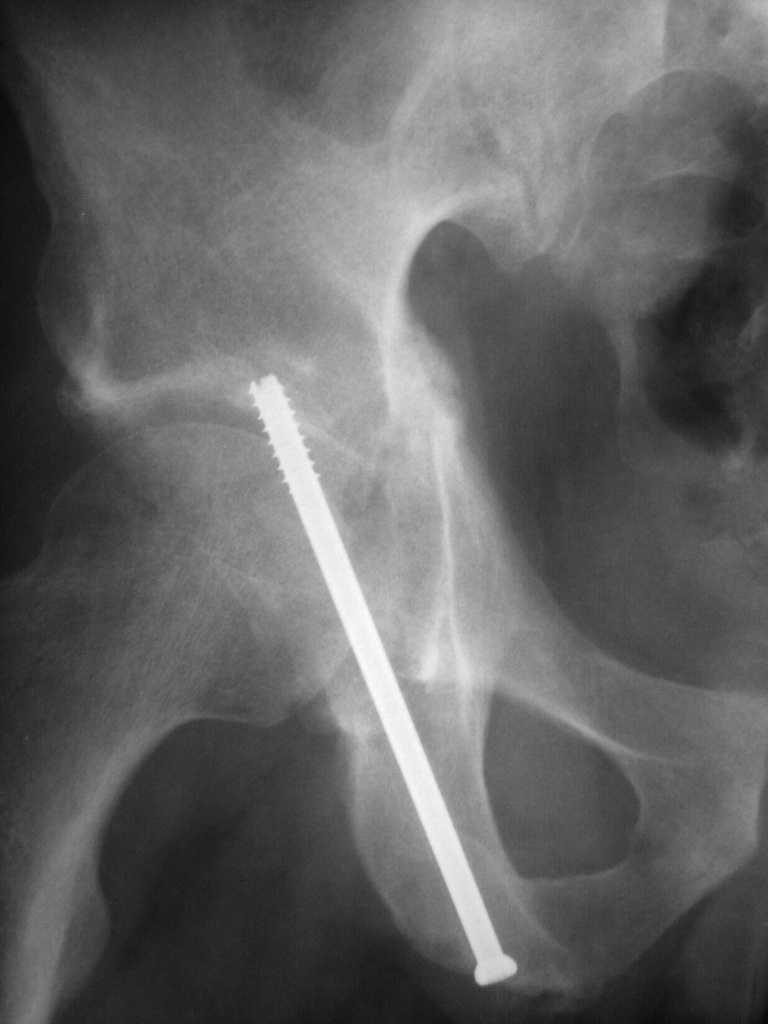

Yordan! In this case position of bone fragments is quite good. We

prefer to use miniinvasive technique. We fix posterior column by can. screw and put 3mm pin with distal thread to the anterior column. Next day after the surgery he may start walking with crutches. 3 month after the surgery we remove the pin. In cases of maleolar fractures we use

angle stable plates to lat. mal. and pins or screws and if syndesmosis is intact - full loading is not forbidden.

Sending exampl pict.